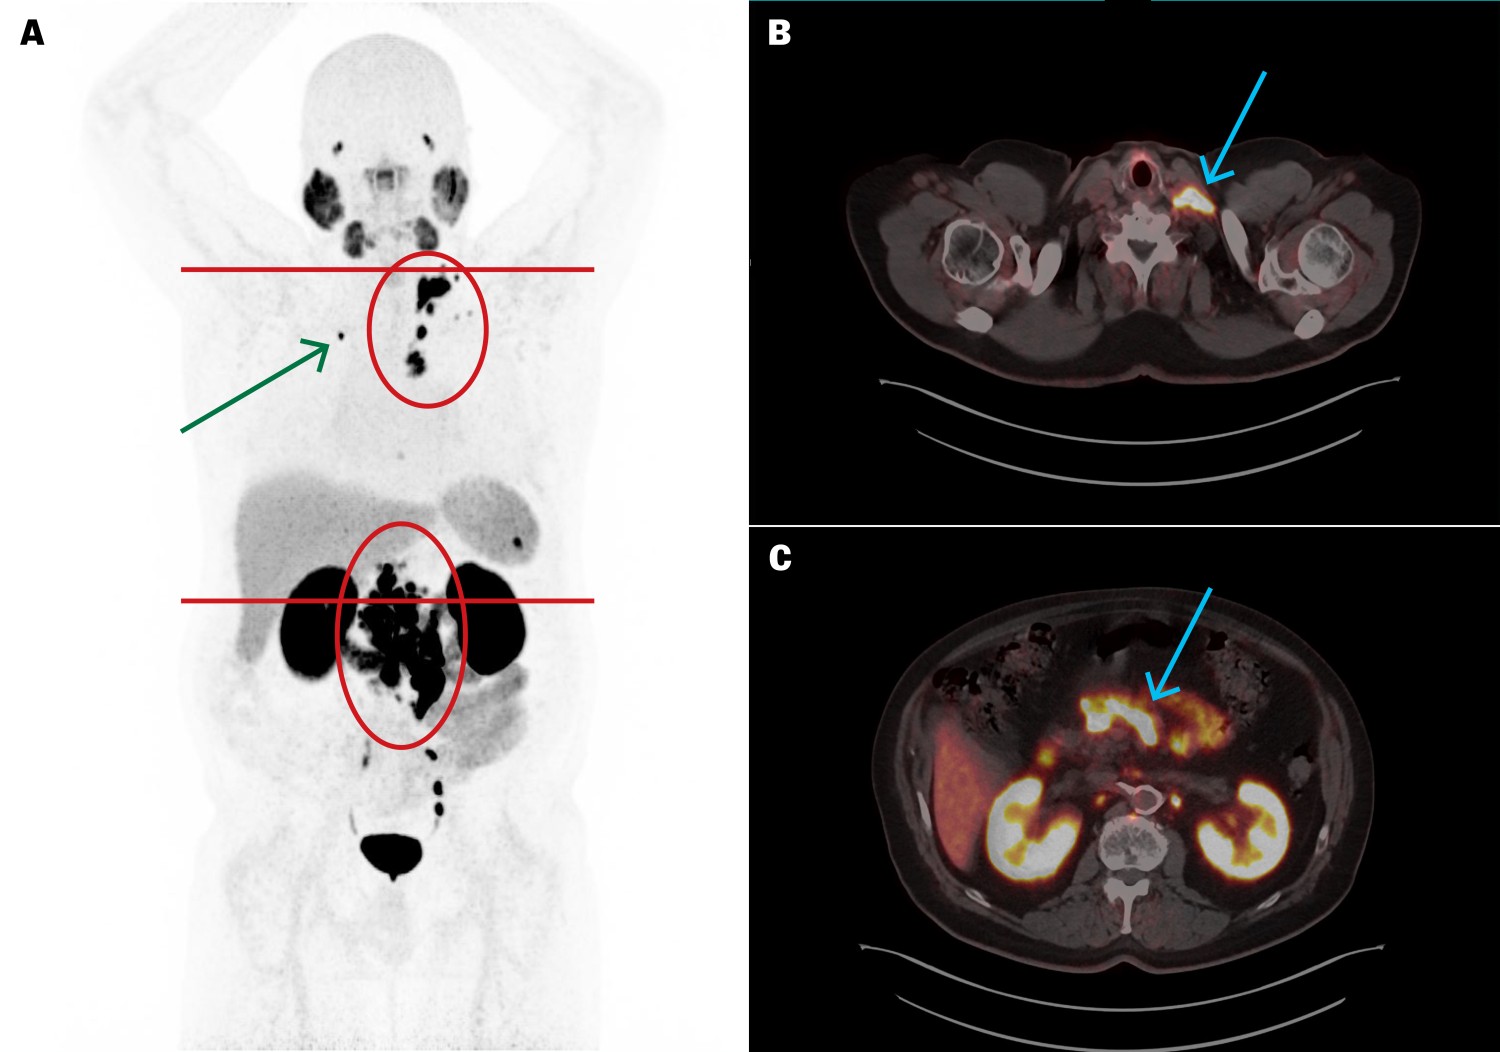

PSA i plasma (p-PSA, referanseområde 0–4,0 µg/L for menn ≥ 60 år) var 154 µg/L og PSA-doblingstiden var 4,5 måneder. PET/CT med det radiofarmasøytiske sporstoffet prostataspesifikt membranantigen radioligand (PSMA-RL) merket med Gallium-68 ([⁶⁸Ga]PSMA-11) viste meget høyt opptak i utbredte metastatiske lymfeknuter i bekken, abdomen, toraks og hals, samt en solitær skjelettmetastase i høyre krageben (figur 1). Opptaket indikerte at det kunne ligge til rette for behandling med PSMA-ligand merket med den beta-emitterende radionukliden Lutetium-177 ([¹⁷⁷Lu]PSMA-RL).

Fem uker etter femte behandling var p-PSA 1,8 µg/L. [⁶⁸Ga]PSMA-11 PET/CT viste betydelig størrelsesreduksjon av metastasene (figur 2), der den største (mållesjon) hadde redusert diameter fra 10 til 4 mm. Ut over nedsatt matlyst og forstoppelse ble behandlingen godt tolerert uten affeksjon av nyre-, spyttkjertel- eller benmargsfunksjon.